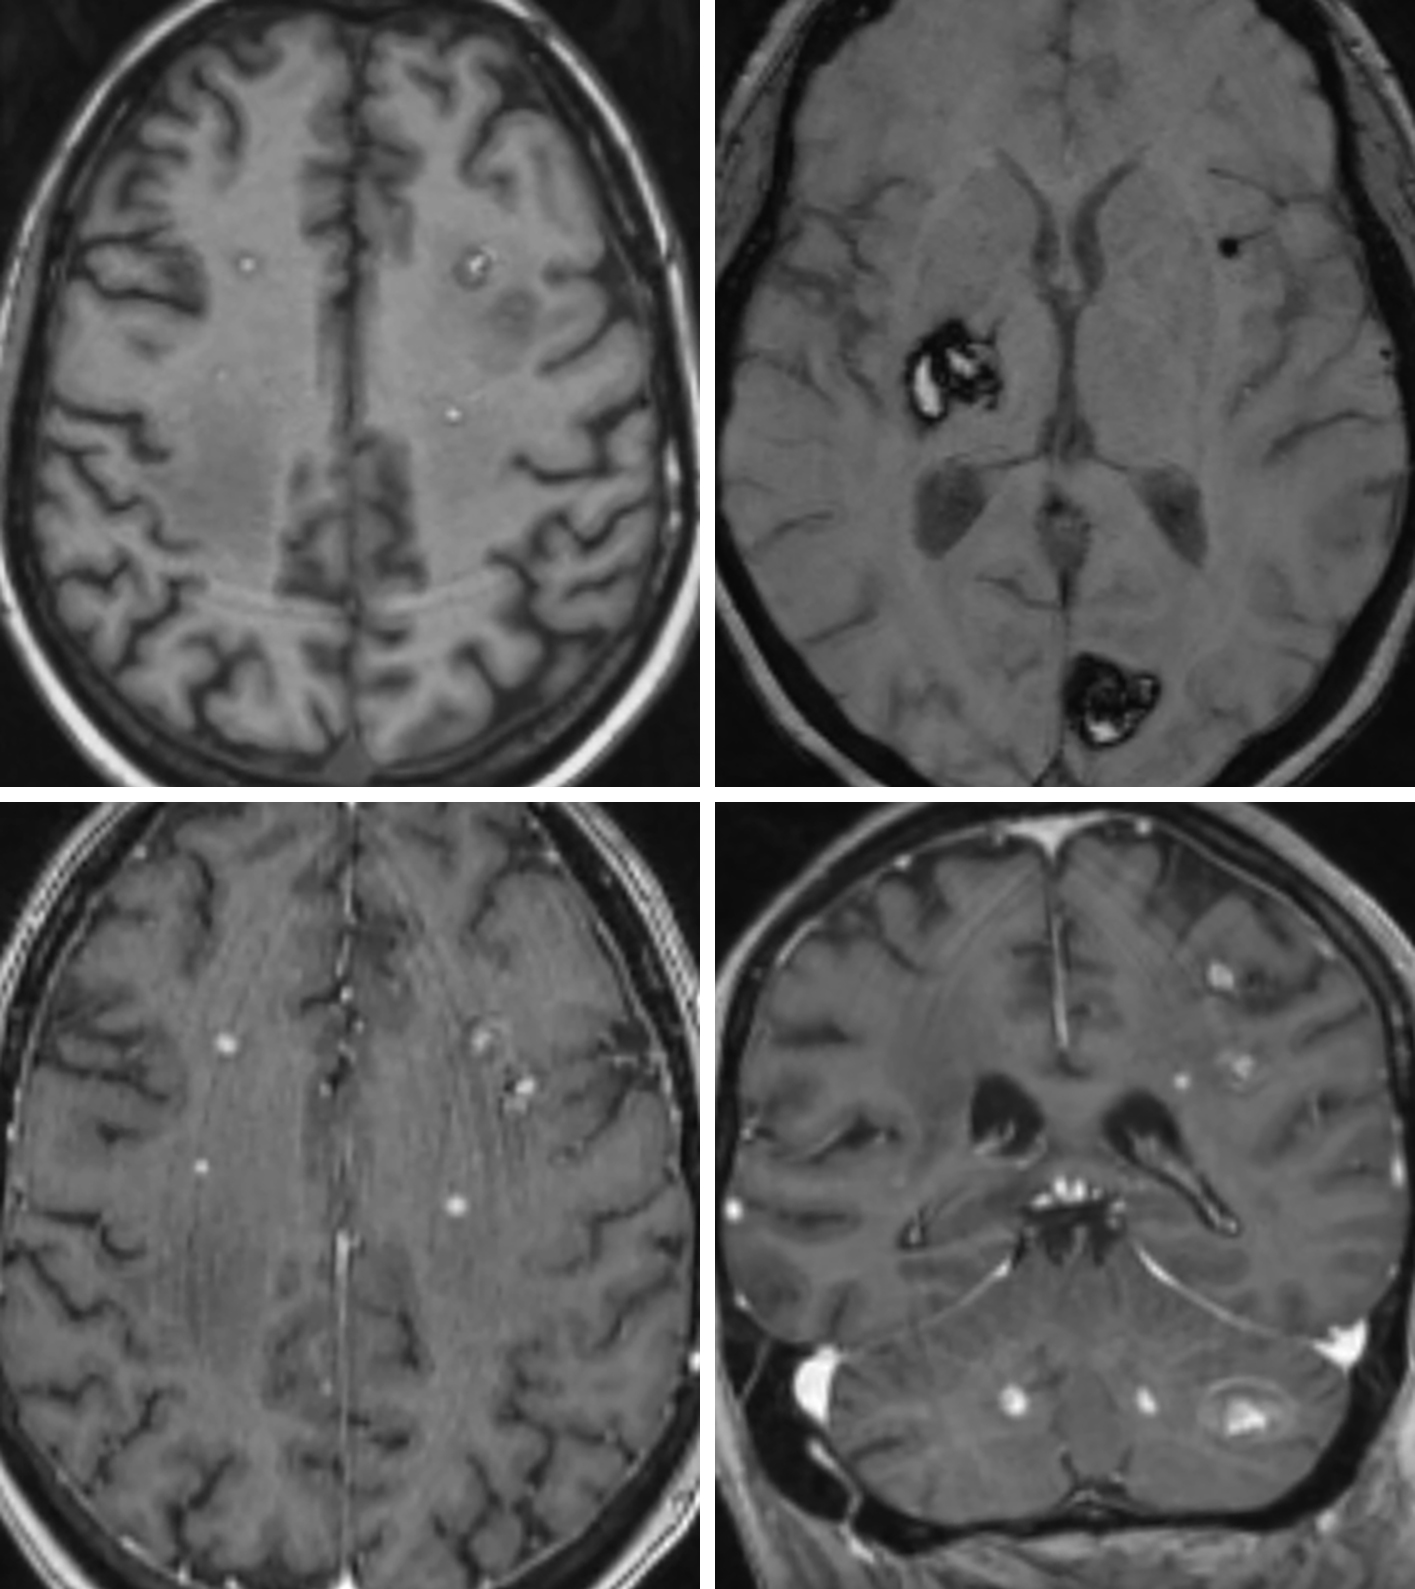

Metastasis | Cohen Collection | Volumes | The Neurosurgical Atlas